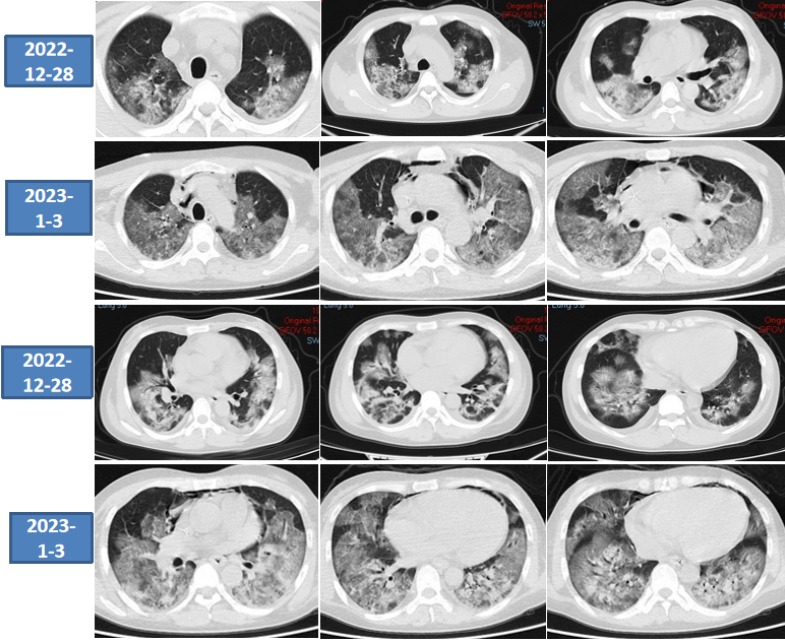

2023年1月6日复查患者胸部CT,已经完全呈“白肺”表现。

图片

调整治疗方案:

原发病——COVID-19危重型:①抗病毒:不需要;②抗炎:巴瑞替尼2 mg qd鼻饲;③抗纤维化:尼达尼布150 mg bid鼻饲;④备肺移植。

呼吸支持:VV-ECMO,警惕气压伤。